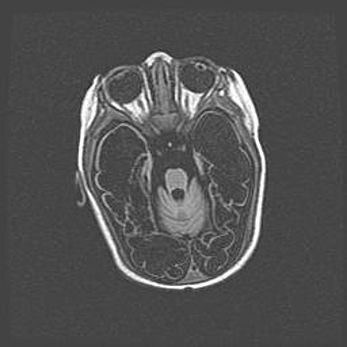

Лейкомаляция с кистозно-глиозной дегенерацией головного мозга.

Возраст: 2 месяца 25 дней

Вес: 6400 г

Окружность головы: 40 см

Срок гестации: 41 неделя

Лейкомаляцию относят к ишемически-гипоксическим повреждениям головного мозга, диагностируемым у новорожденных. При лейкомаляции в головном мозге обнаруживают очаги некроза, возникшие после тяжелой гипоксии и нарушения кровотока. В процессе морфогенеза очаги проходят три стадии: 1) развития некроза, 2) резорбции и 3) формирования глиозного рубца или кисты. Перивентрикулярная лейкомаляция (ПЛ) встречается примерно в 12% случаев среди новорожденных, обычно – у недоношенных детей, причем, частота ее зависит от массы, с которой младенец появился на свет. Наибольшее число малышей страдает лейкомаляцией, если масса при рождении 1500-2500 г.